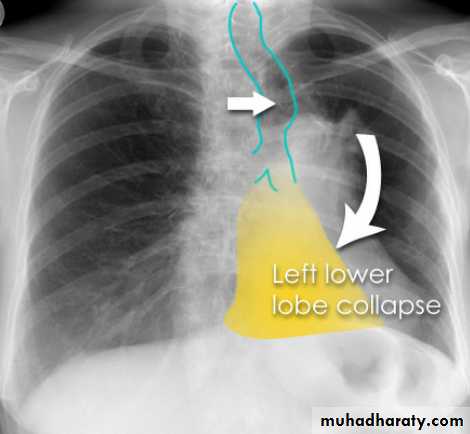

Left lower lobe collapse has distinctive features, and can be readily identified on frontal chest radiographs, provided attention is paid to the normal cardiomediastinal contours. The shadow cast by the heart does however make it harder to see than the right lower lobe collapse

Radiographic features

Left lower lobe collapse

is readily identified in a well penetrated film of a patient with normal sized heart, but can be challenging in the typical patient with collapse, namely unwell patients, with portable (AP) often under-penetrated films, often with concomitant cardiomegaly. Features to be observed include :

triangular opacity in the posteromedial aspect of the left lung

edge of collapsed lung may create a 'double cardiac contour'

left hilum will be depressed

loss of the normal left hemidaphgragmatic outline

loss of the outline of the descending aorta

Non-specific signs indicating left sided atelectasis are usually also be present including:

elevation of the hemidiaphragm

crowding of the left sided ribs

shift of the mediastinum to the left

On lateral projection the left hemidiaphragmatic outline is lost posteriorly and the lower thoracic vertebrae appear denser than normal (they are usually more radiolucent than the upper vertebrae) .